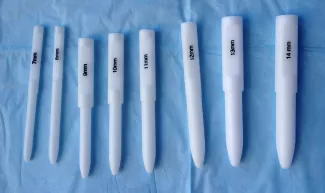

Anal dilation

You will receive a set of anal dilators before you leave the hospital. Bring these to your first surgical appointment. An anal incision will heal by contracting and becoming tight. If this happens, passing bowel movements will be very difficult. Stretching the anal incision gently with anal dilators is required and will begin at your child’s first postoperative visit with the surgeon. You will need to continue the dilations at home. Please follow these instructions carefully as it is essential to prevent a stricture or narrowing of the anal opening. If you are having problems with anal dilation contact the surgical nurse practitioner.

Anal dilation supplies

Dilator, K-Y lubricant, clean diaper, wipes and someone to help you, if needed.

Directions for anal dilations at home

- Position your child on his/her back, holding the feet toward the head with knees flexed.

- Lubricate the dilator and gently insert into the anus.

- Withdraw the dilator. Clean with soap and water (a very small amount of bleeding may occur, this can be normal).

- Use twice daily, for one week.

- Every week, change to a dilator that is one size larger.

- Use twice daily for one week.

- Stop increasing the size once you get to the maximum size as directed by your surgeon.

Tapering dilations

- Continue twice daily dilations for 2 weeks using dilator size as directed by surgeon.

- Decrease frequency to once daily for 2 weeks.

- Decrease to every Monday, Wednesday and Friday for 2 weeks.

- Decease to once a week for 2 weeks.

- Stop dilations.*

*Do not discard your dilators. They are to be cleaned with soap and water and saved in the event they need to be used again.

Guidelines for sizing anal dilators:

- 1-4 Months of age: 12

- 4-8 Months of age: 13

- 8-12 Months of age: 14

- 1-3 Years of age: 15

- 3-12 Years of age: 16

- > 12 years of age: 17–18